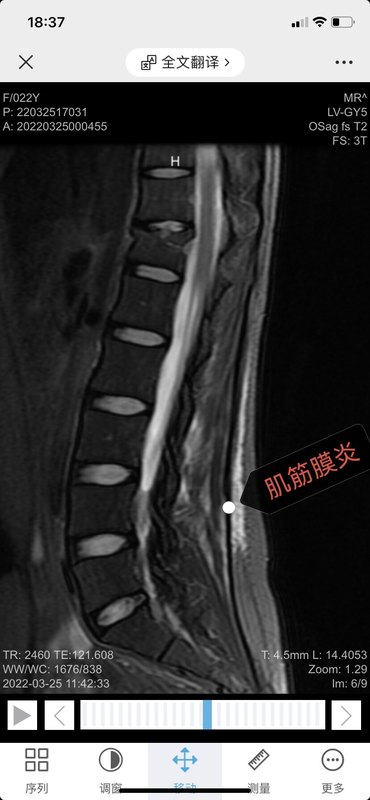

長期不正確的姿勢和負重,肌肉長期處于疲勞狀態(tài),內(nèi)外平衡失調(diào),力量不足,韌帶、筋膜挫傷,肌肉纖維拉傷,甚至出現(xiàn)局部的組織液滲出和微血管破裂,蔓延到鄰近肌間隙后形成瘢痕組織,最終導(dǎo)致局部粘連、變性、甚至肌肉萎縮,也就是肌筋膜炎。分布于肌肉組織中的神經(jīng)纖維受到病變組織的壓迫、刺激甚至部分神經(jīng)末梢被破壞,產(chǎn)生疼痛感。腰部軟組織受到損傷之后未得到及時正確的治療,或治療不徹底,或反復(fù)多次損傷,致使受傷的組織不能完全修復(fù),局部存在慢性無菌性炎癥,微循環(huán)障礙,乳酸等代謝產(chǎn)物堆積,加之受損的肌纖維變性或疤痕化,也可刺激或壓迫神經(jīng)末梢而引起慢性腰痛。兩方面形成惡性循環(huán),使腰背部疼痛日益嚴重。